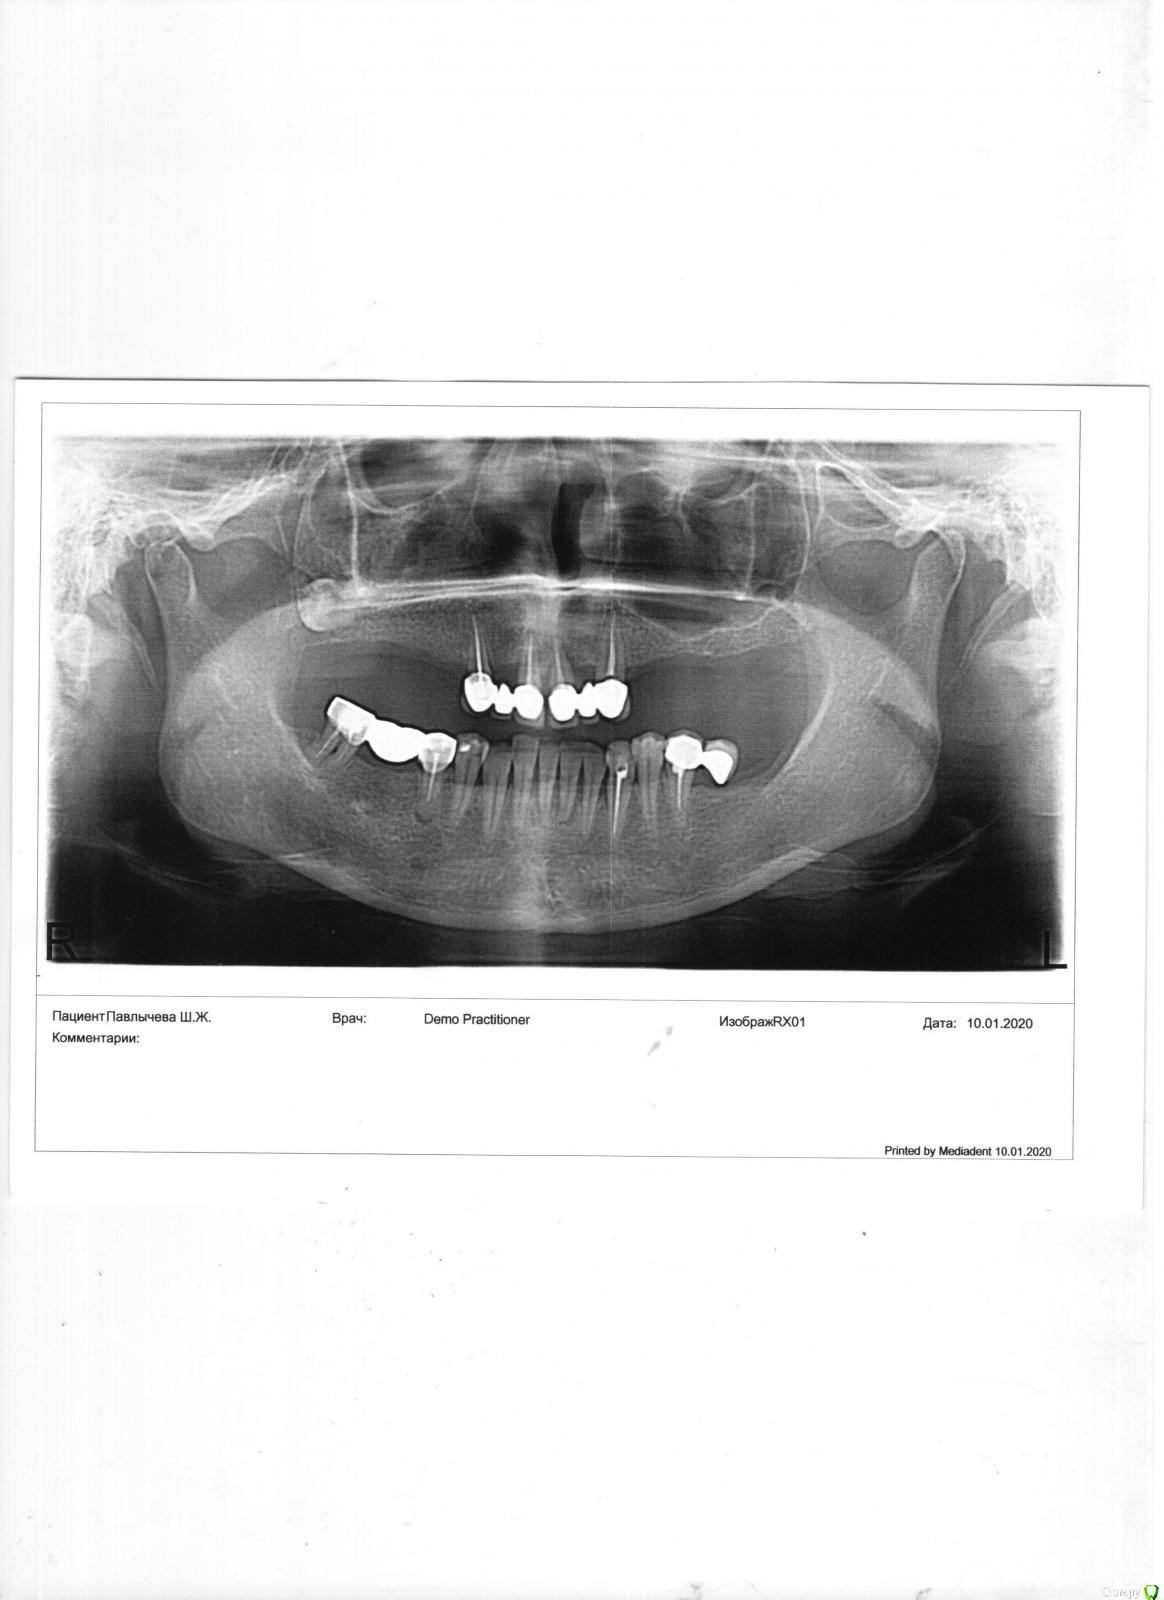

Light70 Опубликовано 14 января, 2020 Поделиться Опубликовано 14 января, 2020 Здравствуйте, требуется независимая консультация и помощь в выборе имплантации. Имеем в анамнезе: в/ч - 4 зуба на воспаленной десне. На приеме у первого стоматолога-протезиста: предлагают удалить несостоятельные зубы, сразу импланты и на атрофированной десне короткие импланты без костной пластики, итого 6 имплантов и протез. На приеме у второго протезиста - полная санация, лечение десен на обеих челюстях, удаление верхних зубов, костная пластика и затем установка 6 имплантов и протез с периодичностью в 4-6 месяцев. Больше склоняюсь ко второму варианту. Во вложении панорамный снимок, качество хромает, но все таки... Ссылка на комментарий

Irouil Опубликовано 14 января, 2020 Поделиться Опубликовано 14 января, 2020 Оба варианта вероятнее всего имеют право на жизнь, но я бы рассматривал в первую очередь одномоментную имплантацию с удалением. Судя по оптг особых проблем с удалением и имплантацией в лунки клыков быть не должно, один или два имплантата в лунку/лунки резцов, дальше еще по 2 имплантата на боковые отделы с каждой стороны, но тут надо на КТ смотреть ширину альвеолярного гребня, небольшой синус лифт с обеих сторон, скорее всего, потребуется, но не должен помешать провести одномоментно нагрузку на имплантаты. В течении недели временный несьемный протез и 4-5 месяцев походить с ним до интеграции 1 Ссылка на комментарий